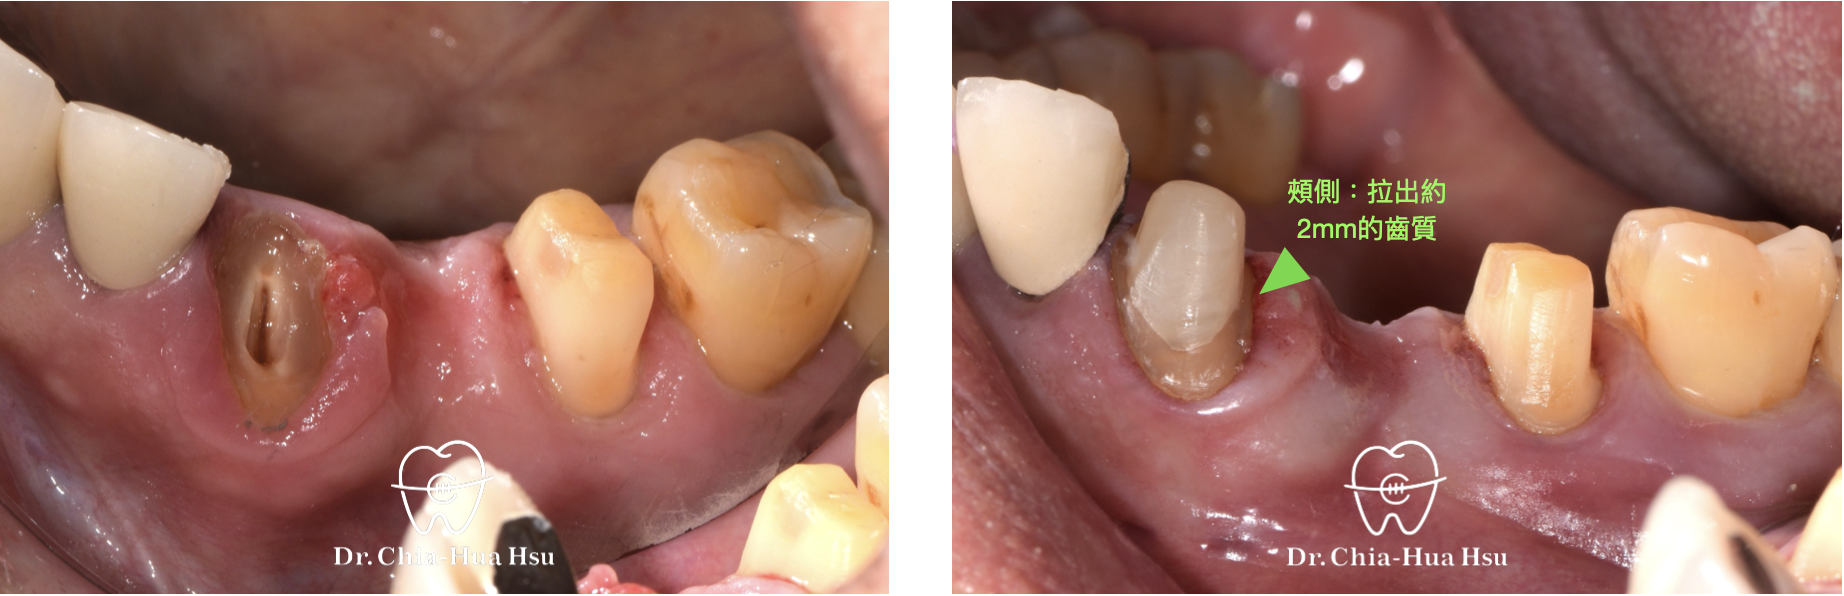

治療前

治療後

• 強逼萌出術 Forced eruption :在臨時牙橋上黏著金屬鈕扣,再使用橡皮圈把殘根牙齒拉出來以獲得足夠齒質(Ferrule effect),以利新的假牙製作。

• 治療結果:拉出足夠齒質高度(Ferrule effect)來製作假牙。